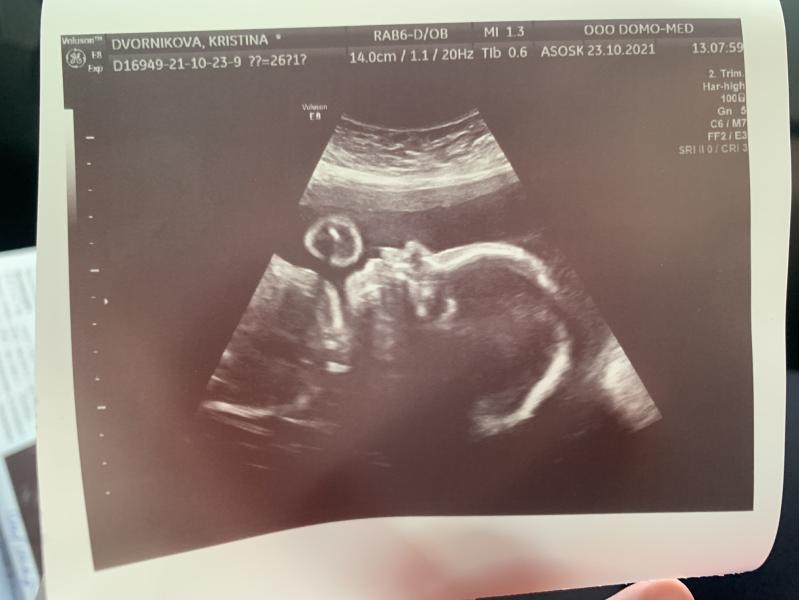

26 неделька 🌸

Наша маленькая принцесса , как и в прошлую беременность ставят сзрп , но мы не слушаем и пускаем мимо ушей 😅 потому что гинетика 🤚 я малявка ростом 157 и родилась маленькая и худенькая , дочь родилась 2600 на 38 неделе )

По узи все отлично вес 770 гр , делали узи с доплером , все 👍 , я немного переживала что могут быть какие -то проблемы после ковидной пневмонии , так как состояние было очень тяжелое .

Все так же краевое предлежание плацента 4 мм от зева , если не поднимется с...